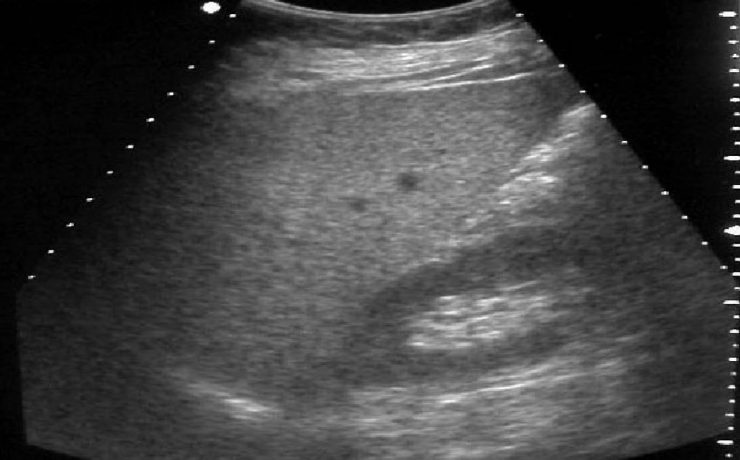

El ultrasonido en algunas afectaciones de la tiroides

La glándula tiroides está ubicada en la región anteroinferior del cuello, en el compartimento infrahioideo. Se halla por delante de los primeros anillos traqueales y de la zona lateral de la laringe. El volumen de la glándula puede ser un poco mayor en la mujer, a pesar que presenta múltiples